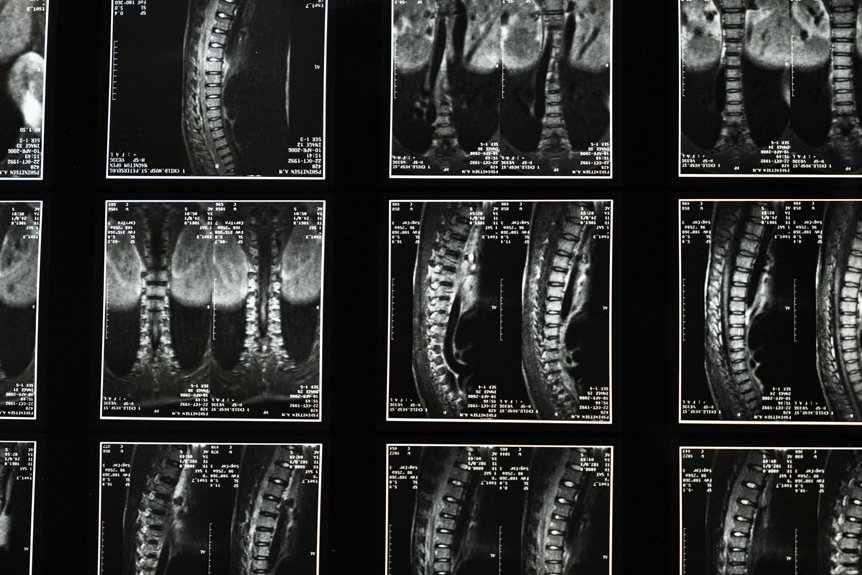

Sciatica occurs when the sciatic nerve becomes irritated or compressed, leading to pain that radiates from your lower back down through your hips and legs. Nerve compression is often the root cause, caused by factors like disc herniation, where a rubbery disc bulges or slips out of place. Chiropractic care can effectively address these issues by relieving nerve pressure through spinal adjustments. This puts pressure on the nerve, triggering sharp, shooting pain. Understanding these causes helps you recognize why your back pain worsens with certain movements.

Disc herniation and nerve compression are common culprits behind sciatica, and identifying them is key to effective treatment. Addressing these issues early can prevent further nerve damage and reduce your discomfort.